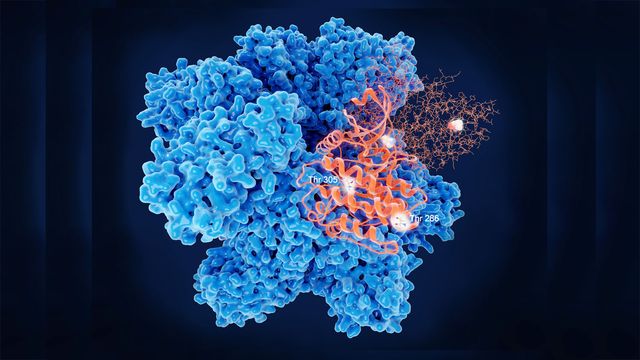

Recombinant Enzyme Development & Production

Producing a recombinant enzyme can be labor-intensive, expensive, and sometimes complicated. SignalChem has over 20 years of expertise in developing enzymes. Let the recombinant enzyme experts at SignalChem make your research easy.

• Extensive experience in creating thousands of active enzymes